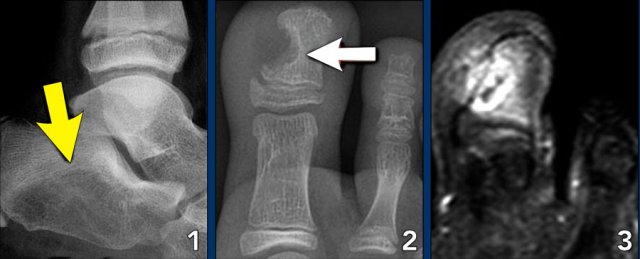

Foot lesions

Here some typical examples of bone tumors in the foot:

1. Geode or subchondral cyst in the navicular bone

2. Geode or subchondral cyst in the tarsal bone

3. Chondroblastoma in the tarsal bone

4. X-ray and MRI of a chondroblastoma in the tarsal bone

5. Chondroblastoma in the tarsal bone

1. Aneurysmal bone cyst in the tarsal bone

2. Chondroblastoma in the tarsal bone

3. Chondromyxoid fibroma (CMF) in the calcaneus

4. Same patient MRI

5. CMF in the second metatarsal bone

1. Ewing sarcoma in the calcaneus

2. Glomus tumor

3. Same patient MRI